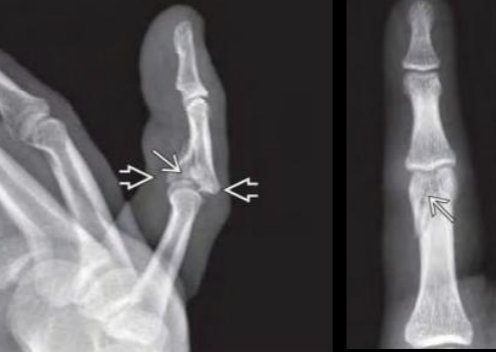

Que pedir en fracturas de falange y metacarpianos?

A

AP y lateral Falanges

AP y oblicua Metacarpianos

Fx falange

How well did you know this?

Fx de falange